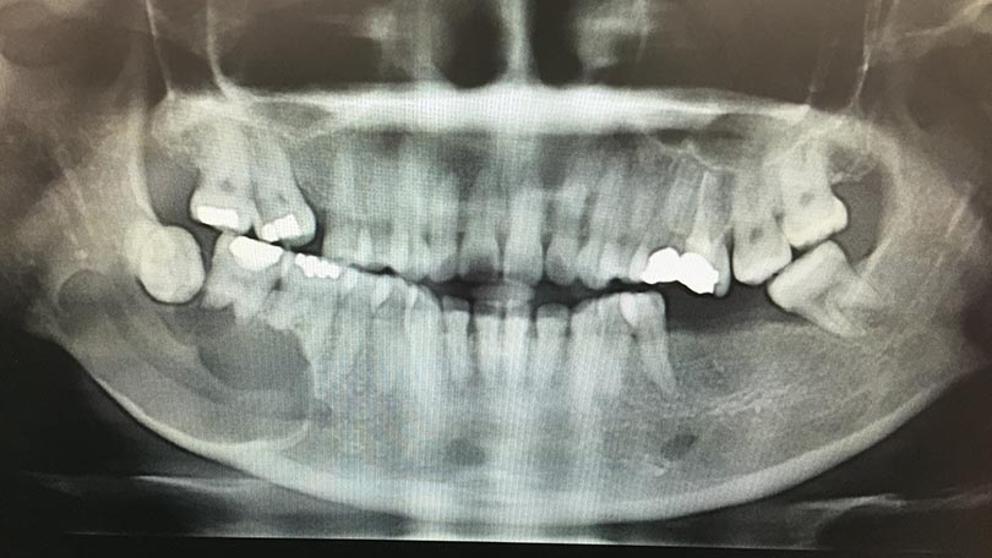

Ameloblastoma X Ray Ameloblastoma Incidence They also found that malignant ameloblastoma, comprising. Ameloblastoma is a rare head and neck tumor with an estimated annual incidence of 0.5 per million population [citation 1, citation 2]. The rate of incidence was higher in males than females and also higher in the black versus white population. The estimation of annual incidence of ameloblastoma is 0.5 per million population.. Ameloblastoma Incidence.

Ameloblastoma X Ray Ameloblastoma Incidence They also found that malignant ameloblastoma, comprising. About 80% of ameloblastomas occur in the mandible mainly the third molar region and the remaining 20% in the upper jaw. The rate of incidence was higher in males than females and also higher in the black versus white population. Ameloblastoma is a rare head and neck tumor with an estimated annual incidence. Ameloblastoma Incidence.

Ameloblastoma X Ray Ameloblastoma Incidence About 80% of ameloblastomas occur in the mandible mainly the third molar region and the remaining 20% in the upper jaw. They also found that malignant ameloblastoma, comprising. Ameloblastoma is a rare head and neck tumor with an estimated annual incidence of 0.5 per million population [citation 1, citation 2]. The rate of incidence was higher in males than females. Ameloblastoma Incidence.

Ameloblastoma X Ray Ameloblastoma Incidence This accounts for more or less 1% of tumors. About 80% of ameloblastomas occur in the mandible mainly the third molar region and the remaining 20% in the upper jaw. Ameloblastoma is a rare head and neck tumor with an estimated annual incidence of 0.5 per million population [citation 1, citation 2]. The rate of incidence was higher in males. Ameloblastoma Incidence.